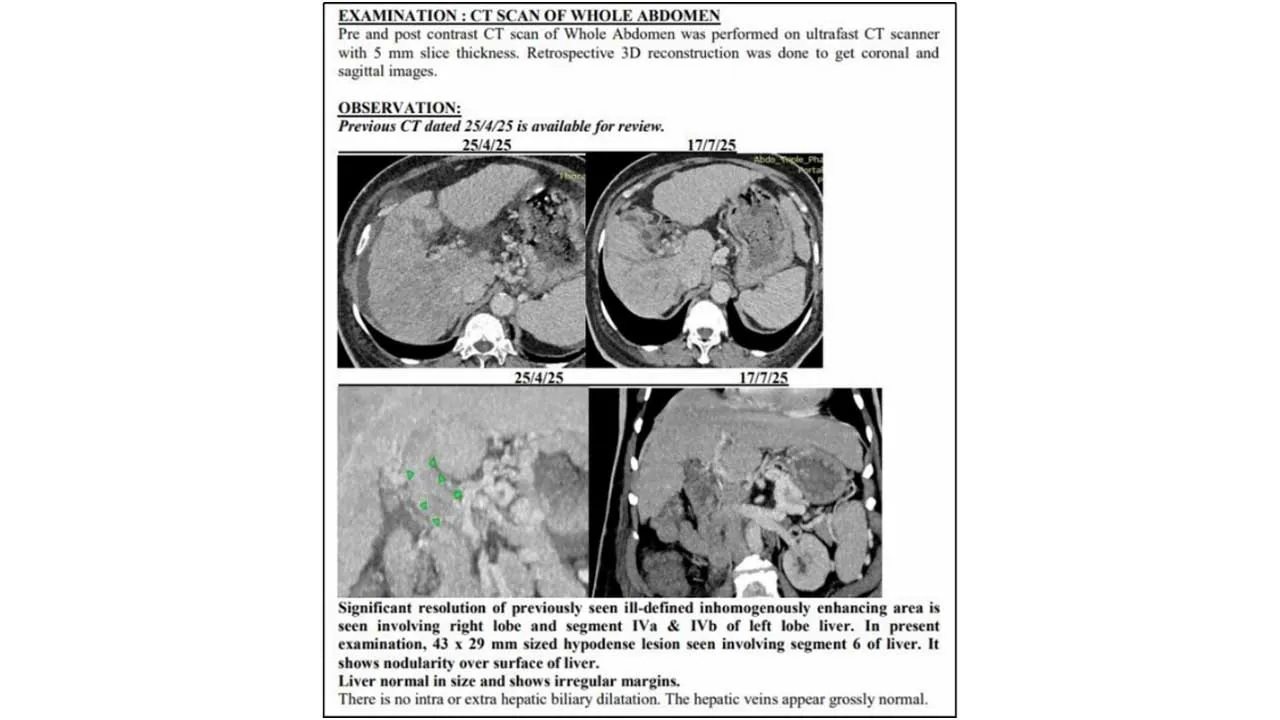

પરંતુ માત્ર ત્રણ મહિનામાં, જુલાઈની બપોરે, પરિવારએ બીજો સ્કેન જોયો – ટ્યુમર ઘટીને એક જ પેચમાં સીમિત, નસોમાં ફરીથી લોહી વહેવાનું શરૂ, પાણીનો ભરાવો ગાયબ. ટ્યુમર માર્કર 1,000 ng/mLથી ઘટીને 10 પર આવી ગયો. પરિવાર માટે આ ચોંકાવનારો વળાંક હતો.

જુલાઈના સિટી સ્કેનમાં સાબિત થયું – ટ્યુમર ઘટીને નાના થયા, પેટનું પાણી ખતમ, તમામ આંકડા નોર્મલ. એક વરિષ્ઠ રેડિયોલોજિસ્ટે જણાવ્યું: “આવી રિવર્સલ એડવાન્સ લિવર કેન્સરમાં અતિશય દુર્લભ છે. લગભગ અવિશ્વસનીય.”